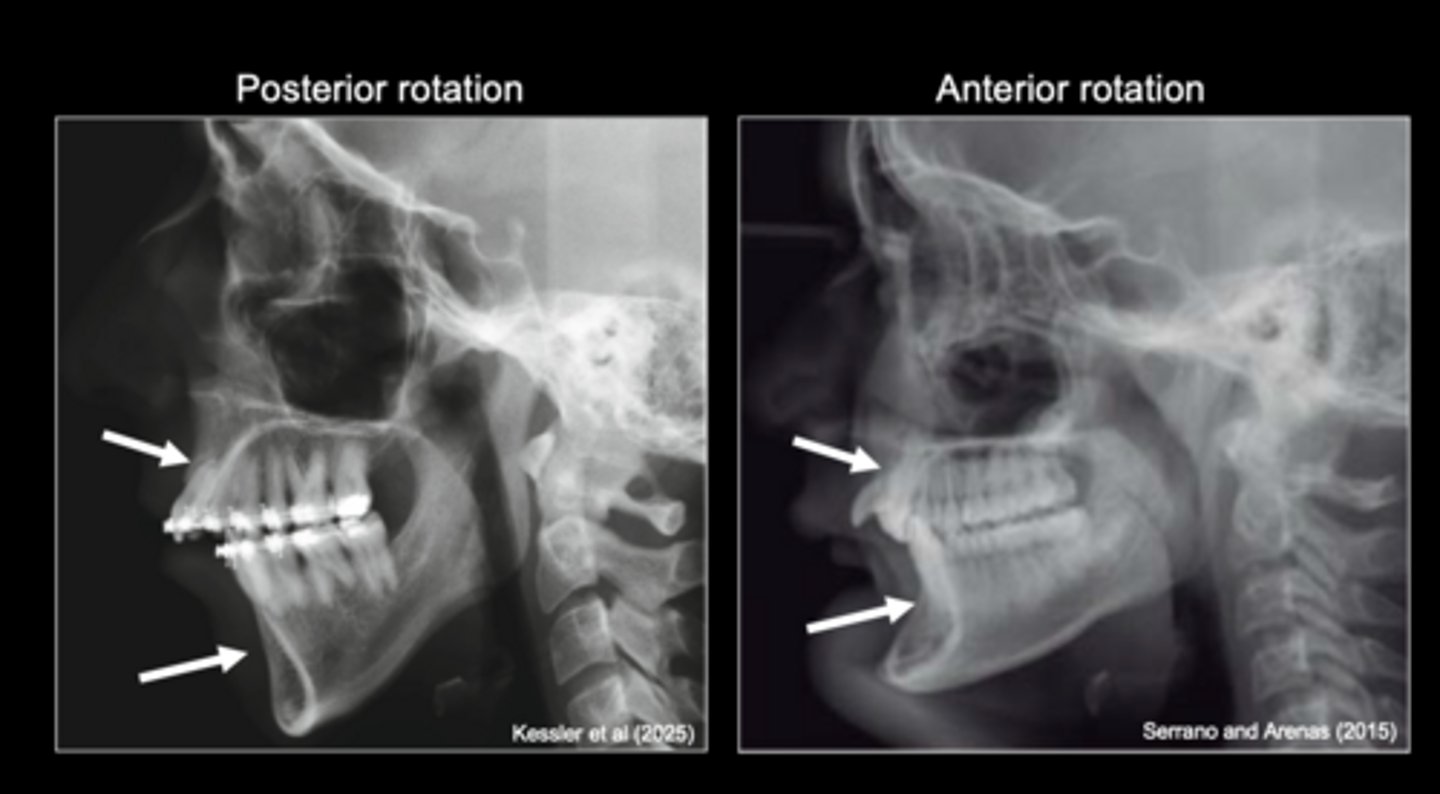

different patterns of mandibular rotation

Variation in condylar cartilage growth results in

different condylar cartilage does this shit

knowt flashcard image

condylar cartilage (on the right)

- not in a columnar arrangement thus can grow in different directions

The potential for different patterns of mandibular rotation is evident in the

<p>The potential for different patterns of mandibular rotation is evident in the</p>

alveolar bone

Mandibular rotation produces compensatory changes in

<p>Mandibular rotation produces compensatory changes in</p>

patterns of mandibular rotation

Variation in respiratory function affects

Variation in masticatory function affects